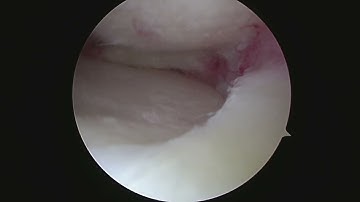

Partial Meniscectomy